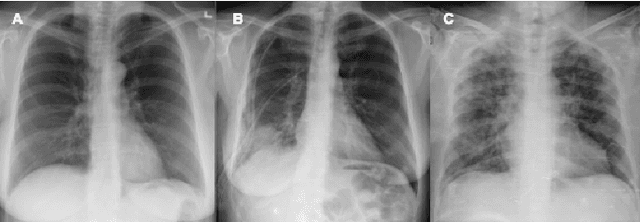

Abstract:After more than two years since the beginning of the COVID-19 pandemic, the pressure of this crisis continues to devastate globally. The use of chest X-ray (CXR) imaging as a complementary screening strategy to RT-PCR testing is not only prevailing but has greatly increased due to its routine clinical use for respiratory complaints. Thus far, many visual perception models have been proposed for COVID-19 screening based on CXR imaging. Nevertheless, the accuracy and the generalization capacity of these models are very much dependent on the diversity and the size of the dataset they were trained on. Motivated by this, we introduce COVIDx CXR-3, a large-scale benchmark dataset of CXR images for supporting COVID-19 computer vision research. COVIDx CXR-3 is composed of 30,386 CXR images from a multinational cohort of 17,026 patients from at least 51 countries, making it, to the best of our knowledge, the most extensive, most diverse COVID-19 CXR dataset in open access form. Here, we provide comprehensive details on the various aspects of the proposed dataset including patient demographics, imaging views, and infection types. The hope is that COVIDx CXR-3 can assist scientists in advancing computer vision research against the COVID-19 pandemic.